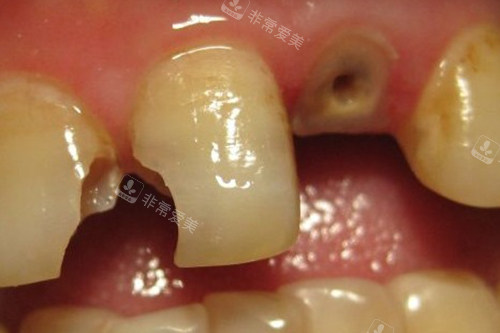

牙齿龋坏到牙根

张氏口腔:口碑传承与创新发展

张氏口腔在蓝山县已经营多年,凭借良好的口碑赢得了众多患者的信赖。

多年来,他们一直坚持诚信行医,以优质的医术和合理的收费,为当地居民解决了无数口腔难题。

随着口腔医学的不断发展,张氏口腔也在不断创新和进步。

他们引进了可靠的口腔诊疗技术和设备,如智能化口腔影像系统、不痛治疗技术等,提高了诊断的比较准性和治疗的结果。